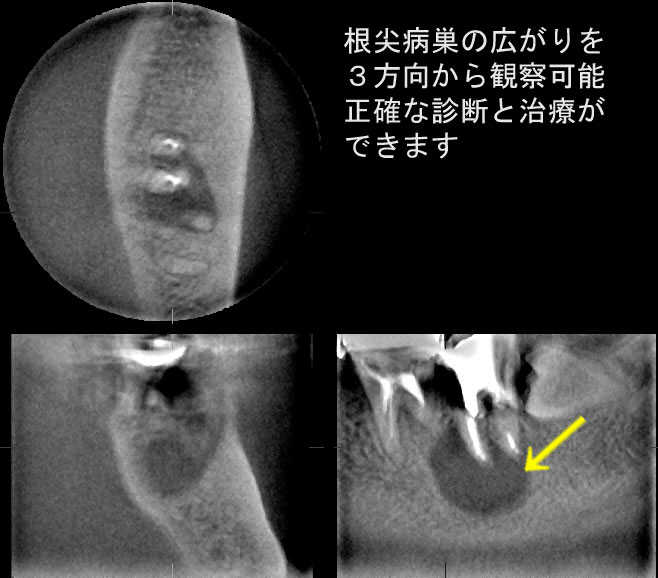

また、平面レントゲンやCT画像では完全な根充と見なされる症例でも根尖部に病巣のある症例がしばしば見られます。(参照:Phot3,Phot4) これらの画像から判明するように複雑な根管形態に完全な根充を行うことは神業といえます。

複雑多様な歯髄形態に拡散している細菌を完全に制圧することが困難であることは事実です。同様に根充もCTで観察すれば明白なように、完璧とおもっても隙間が生じます。しかし、根管治療において病原菌除菌が可能な限り十分におこなっていた場合、修復行為にすぎない根充のテクニックを病的にこだわる必要はないと43年の臨床経験から思います。結果は心身の条件と根尖周囲の組織の抵抗力が決めるようです。